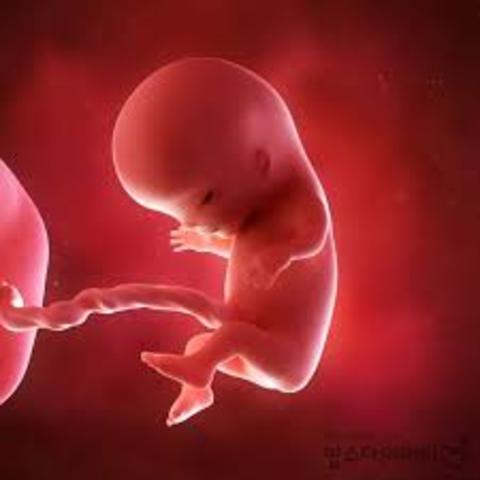

• Day 50

Day 50

Genitalia begins to differentiate, eyelids fuse, amnion surrounds fetus

• Fetal stage begins

Occurs when all organs are formed

Amniocentesis can be performed